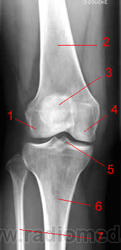

Область коленного сустава.

1, Боковой (латральный) мыщелок бедренной кости.

2, Бедренная кость.

3, Надколенник.

4, Медиальный мыщелок бедренной кости.

5, Межмыщелковое возвышение.

6, Б/берцовая кость.

7, М/берцовая кость.